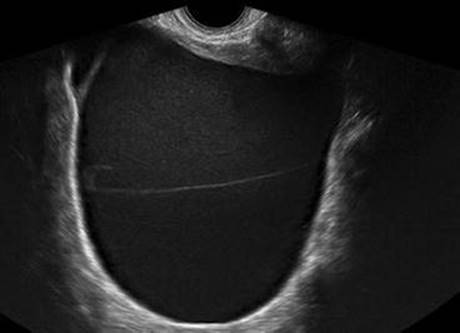

Fig. 4.8

Mucinous cystadenoma by transvaginal ultrasound (Reprinted from Coccia et al. [74], Figure 9, with kind permission from Springer Science and Business Media)